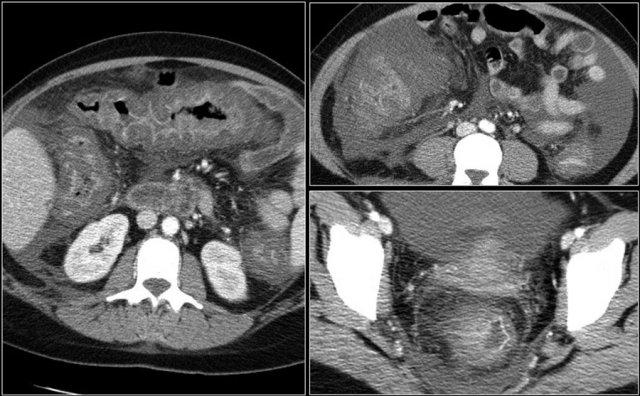

Các hình ảnh này thuộc về bệnh nhân bị tắc ruột non dạng quai kín.

Lưu ý nhóm các quai ruột non có thành dày ở vùng bụng trên phải (mũi tên vàng).

Phù nề mạc treo ruột (mũi tên đỏ) cho thấy tình trạng tăng áp lực tĩnh mạch do thắt nghẹt.

Giãn mạch máu

Tăng áp lực tĩnh mạch trong thắt nghẹt cũng dẫn đến giãn tĩnh mạch (mũi tên vàng).

Bệnh nhân này cũng có tắc ruột dạng quai kín với kiểu ngấm thuốc xám của các quai ruột bị thắt nghẹt (mũi tên đỏ).

Lưu ý sự ngấm thuốc bình thường của ruột non ở phía trên vị trí tắc nghẽn (mũi tên xanh lá).

Một bệnh nhân khác với hình ảnh ruột thiếu máu cục bộ và phù nề mạc treo ruột lan rộng.

Trong phẫu thuật, toàn bộ đoạn ruột non này đã bị hoại tử.